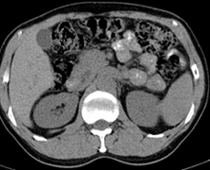

患者,男,57,常年不吃午饭,近一个月来腹部隐痛,无明显黄疸,明天进行增强扫描,图象另上传,麻烦各位帮忙一起看看讨论讨论

肝外胆管扩张,胰头增大,肠系膜上静脉似有包埋征象。

考虑:胰头占位性病变,建议增强进一步检查。

肝外胆管稍扩张,胰腺钩突略增大,但外形尚可,境界清楚。(常年不吃午饭)提示胰腺炎可能大,肿瘤第二步考虑。

支持考胰头占位性病变,感觉十二指肠壁不规则增厚,不排除十二指肠降部占位可炎症

胰头增大,胆总管增宽,考虑胰头癌可能性大,明天看增强片有助诊断.